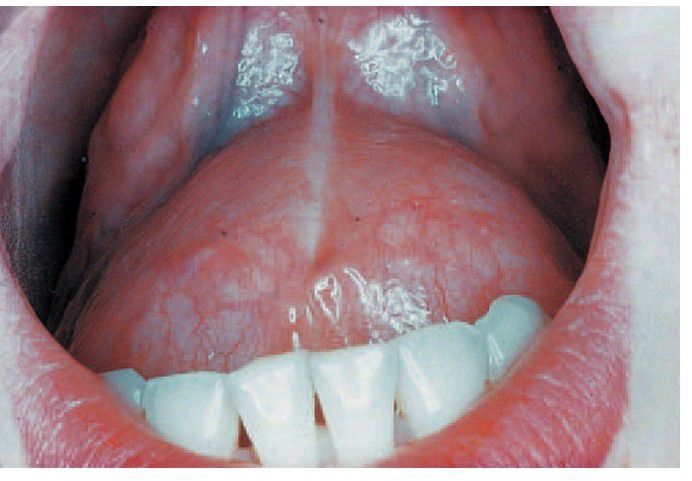

. This is an unusually large specimen but appears even larger because the patient is raising and protruding her tongue. This cyst, unlike a ranula, can be seen to have a thick wall because it has arisen in the deeper tissues of the fl oor of the mouth.